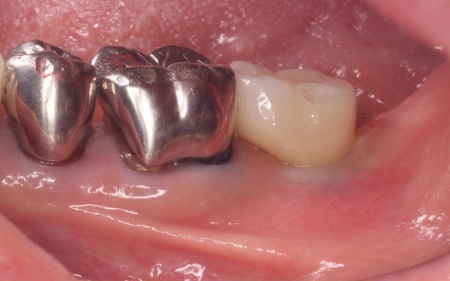

| 診断 | 拝見したところ、左下の一番奥の歯(第2大臼歯)の歯茎に腫れが認められました。 レントゲン撮影を行って詳しく調べたところ、歯根が縦方向に割れている「歯根破折」が疑われる状態です。 歯根破折は、過去に神経の治療を行った歯に起こりやすいトラブルで、今回のケースでは被せ物の下で破折が進行していたと考えられます。 このまま放置すると、痛みや腫れを繰り返すだけでなく、周囲の骨が溶けて隣接する歯にも悪影響を及ぼすおそれがあるため、抜歯の必要があると診断しました。 |

治療前

歯根破折が疑われました。